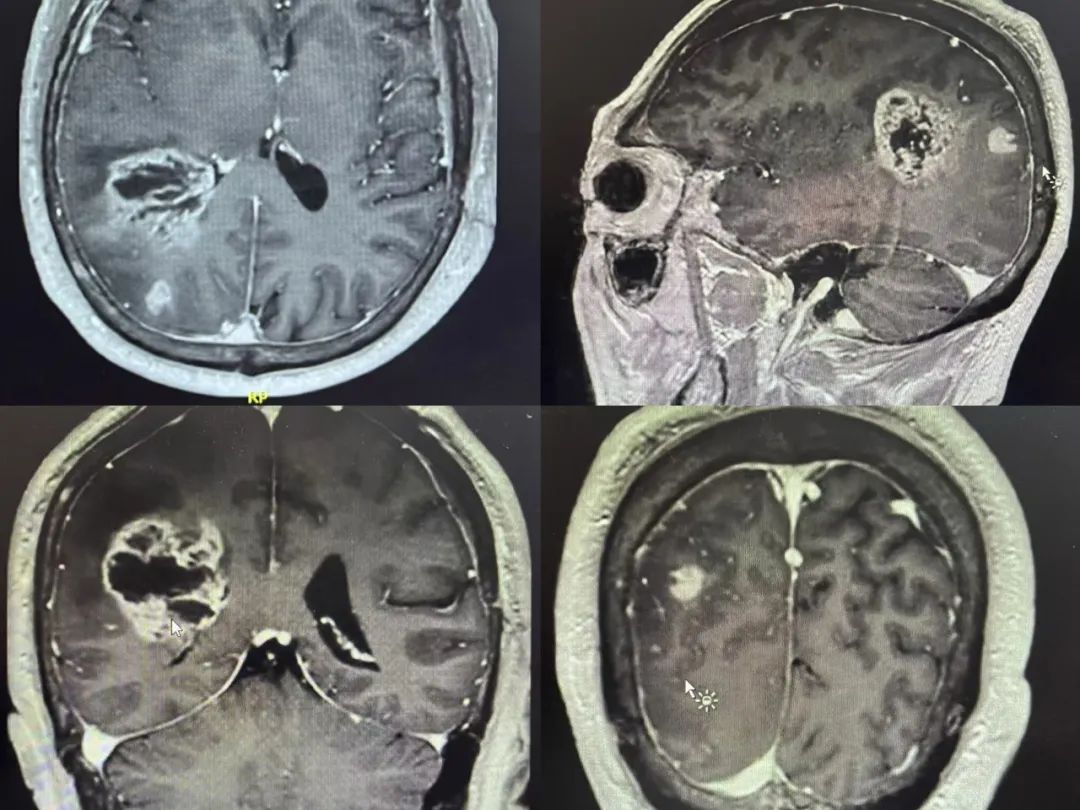

男性 | 62歲

主訴:頭痛1周余。

MR:右側(cè)頂葉占位性病變,考慮膠質(zhì)瘤可能性大。